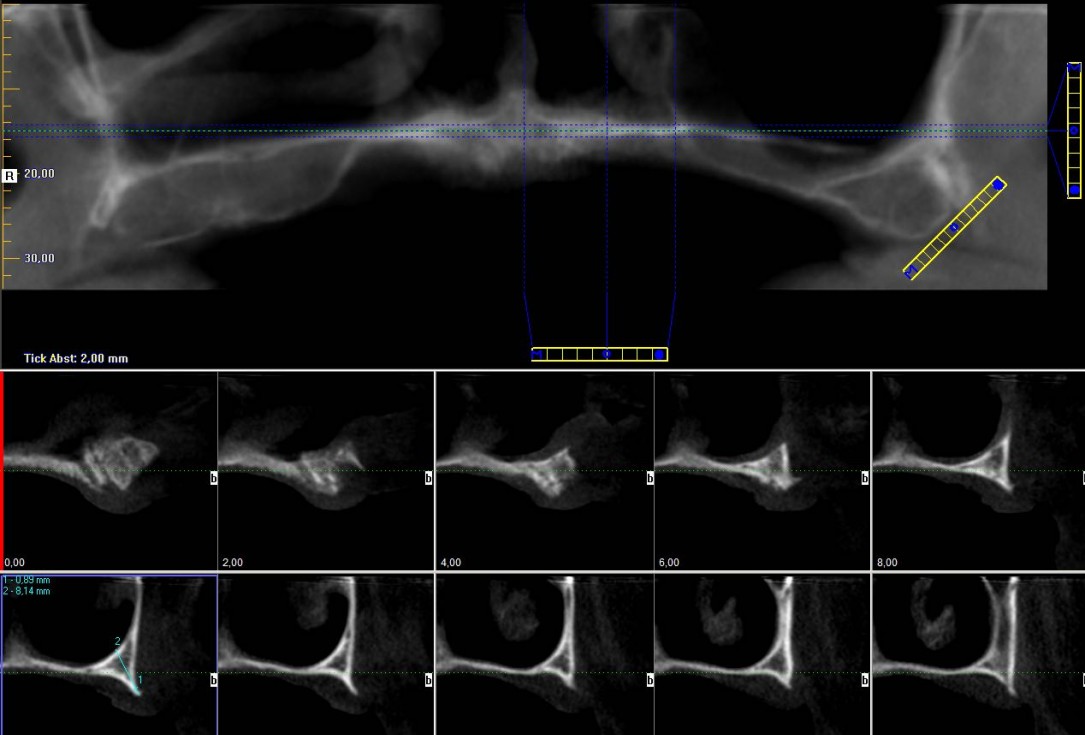

2/23 - Preoperative radiological situation – severely atrophic maxilla

Full arch reconstruction of the maxilla with maxgraft® bonebuilder - Dr. M. Erbshäuser

3/23 - Preoperative radiological situation – severely atrophic maxilla

4/23 - Preoperative radiological situation – severely atrophic maxilla